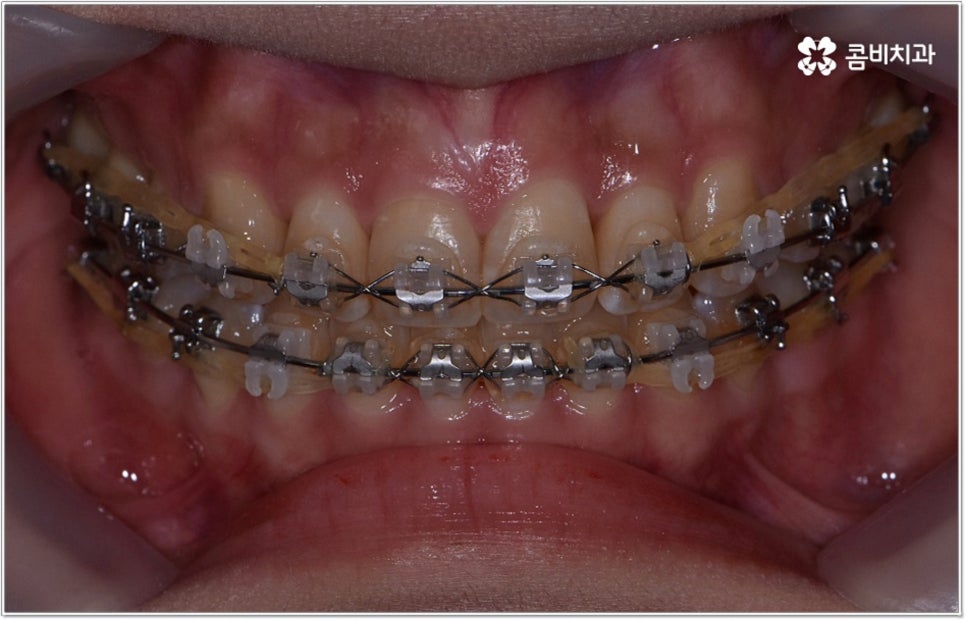

잘 아시다시피 교정이란 치아에 교정 장치 (브라켓) 를 부착하고 와이어에 교정력을 걸어 필요한 방향으로 치아를 이동시킴으로써 고른 치열과 올바른 교합을 가진 정상적인 구강 구조를 회복하는 치과 진료를 의미하는데요, 말씀드린 것처럼 부정교합에는 다양한 형태가 있고 또한 환자분들마다 심각한 정도가 모두 다르기 때문에 현 상태를 면밀하게 체크하고 맞춤 교정 치료 계획을 세우는 것이 무엇보다 중요하다고 할 수 있습니다. 즉 3D CT 와 같은 정밀 진단 장비를 갖추고 있는 치과에서 교정 관련 임상 경험이 풍부한 숙련된 의료진과 함께 치료를 진행하는 것이 필수적이라고 할 수 있어요. 전체 방향 및 세부 플랜을 세울 때 각 환자에 맞게 치아의 이동 속도에 무리가 가지 않도록 하기 위해서 연령이나 발달 상황, 진행 상황을 면밀하게 살펴보는 것이 필요하며 또한 구강 내 공간 유무 및 부정교합 정도에 따라 발치 또는 비발치치아교정 여부를 결정하게 될 거예요.

만약 치아가 이동할 범위를 계산해 봤을 때 공간이 충분하다면 굳이 치아를 뽑지 않고 비발치치아교정 과정으로 치료할 수 있어요. 제일 뒤에 있는 어금니를 더 후방으로 이동시키거나 치간 삭제, 악궁확장장치 등으로 치아 사이를 벌려서 이동 공간을 확보할 수 있으면 비발치치아교정 이 가능한 거예요. 이 때 부정교합이 심각하거나 악골이 치아에 비해 많이 작은 경우, 구조적인 원인을 개선할 필요성이 있는 경우 등 발치 교정을 하는 것이 꼭 필요한 케이스라면 치아를 뽑아주어야 하며, 환자분들의 상황에 따라 다르지만 보통은 소구치를 발치하는 경우가 많이 있습니다.

대다수의 환자분들은 되도록 치아를 뽑지 않았으면 하고 바라시겠지만 발치교정이 꼭 필요한 케이스에서 비발치치아교정 을 고집하게 되면 치열을 원하는 정도까지 움직이기 어렵고 (예를 들어 만약 돌출입이라면 만족할 만한 수준까지 들어가지 않을 수도 있음) 결과적으로 상하 부정 교합 역시 제대로 개선되지 않을 수 있어요. 이 때 다양한 케이스를 다뤄보고 뛰어난 노하우를 가지고 있는 의료진과 충분히 상담을 해 보시고 또한 모르페우스를 이용하여 교정 치료를 받고 난 후의 미래 예상 모습을 살펴 보고 나면 발치 과정의 필요성에 대해 스스로 이해하는데 도움이 되실 거예요.